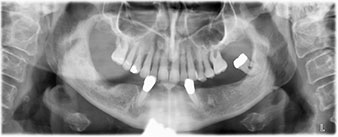

La paziente, 64 anni, presenta una dentatura residua di denti 38, 33 e 43 e una protesi combinata innestata nella mandibola (Fig. 1 e 2).

È stata eseguita una tomografia computerizzata Dentale Cone Beam in 3D (CBCT, con Planmeca) per aiutare la programmazione dell'intervento e la riduzione di rischi. L'esame ha evidenziato che la qualità e quantità dell'osso disponibile era sufficiente per eseguire l'intervento e la ricostruzione immediata, utilizzando il metodo Fast & Fixed. In base al protocollo del sistema, gli impianti sono stati inseriti in posizione 35, 32, 42 e 45. Gli impianti distali vengono installati a un angolo massimo di 45 gradi. Così facendo, il profilo che ne risulta viene spostato in posizione posteriore, generando un poligono di supporto più ampio (Fig. 3).